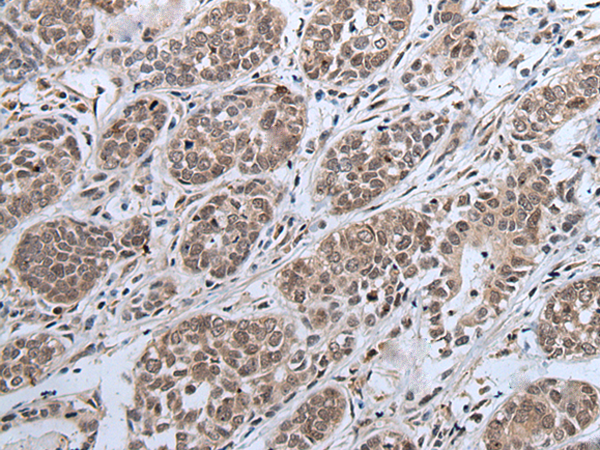

分类: 科研抗体货号: P12880别名: WAP14; dJ447F3.3应用: IHC反应种属: Human